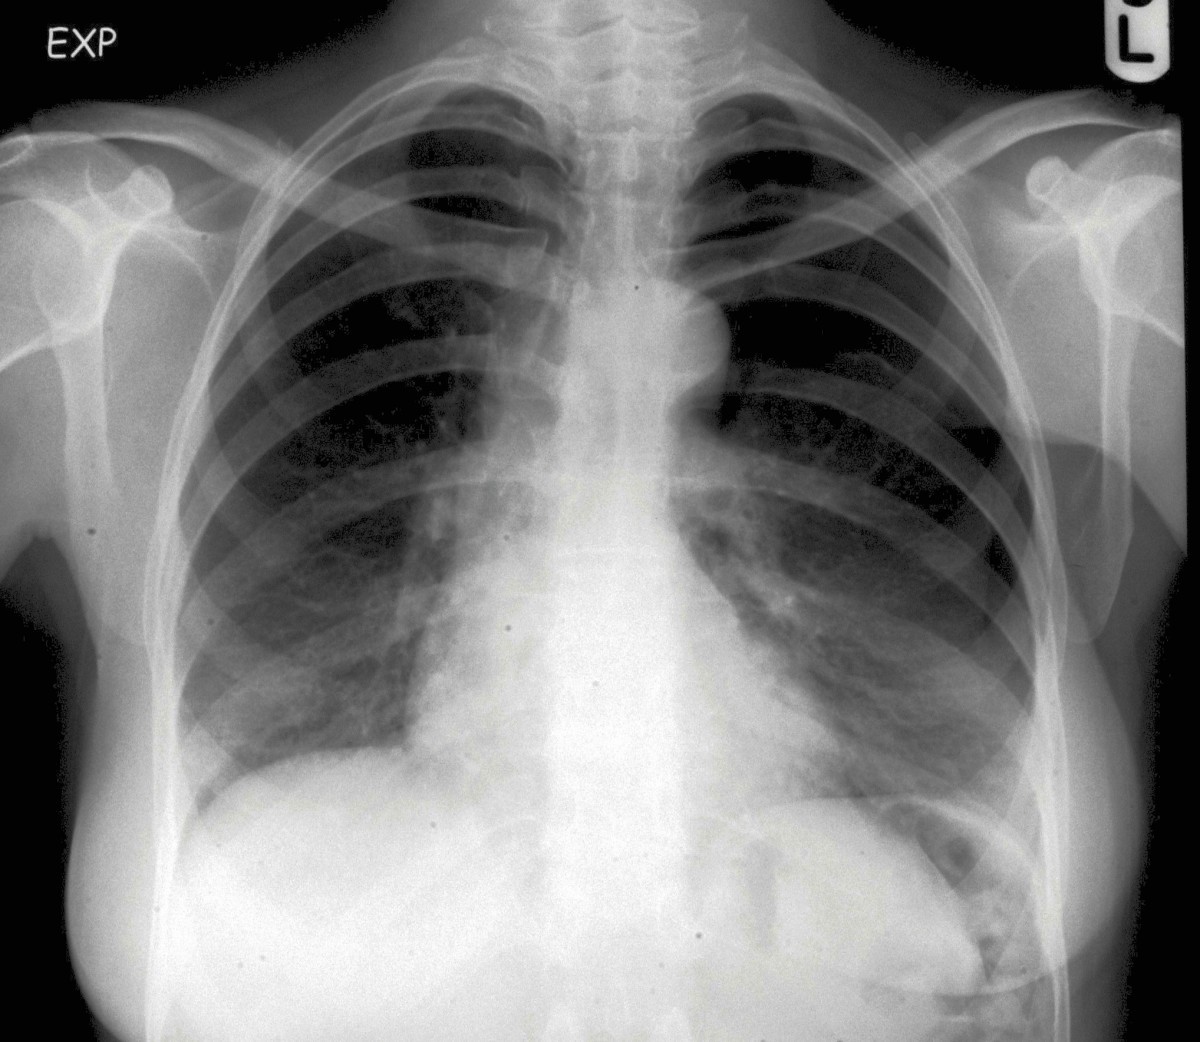

Needle insertion into the lesion close to hila, no pneumothorax

Needle insertion into the lesion close to hila, no pneumothorax What Is Needle Aspiration Pneumothorax a pneumothorax is a collection of air between the parietal and visceral. a pneumothorax is a collection of air inside the pleural space, which is the space between the lungs and chest wall (figure 1). leibel and vachharajani provide a useful, detailed description of needle aspiration of pneumothorax, using a. a pneumothorax is an accumulation of. What Is Needle Aspiration Pneumothorax.